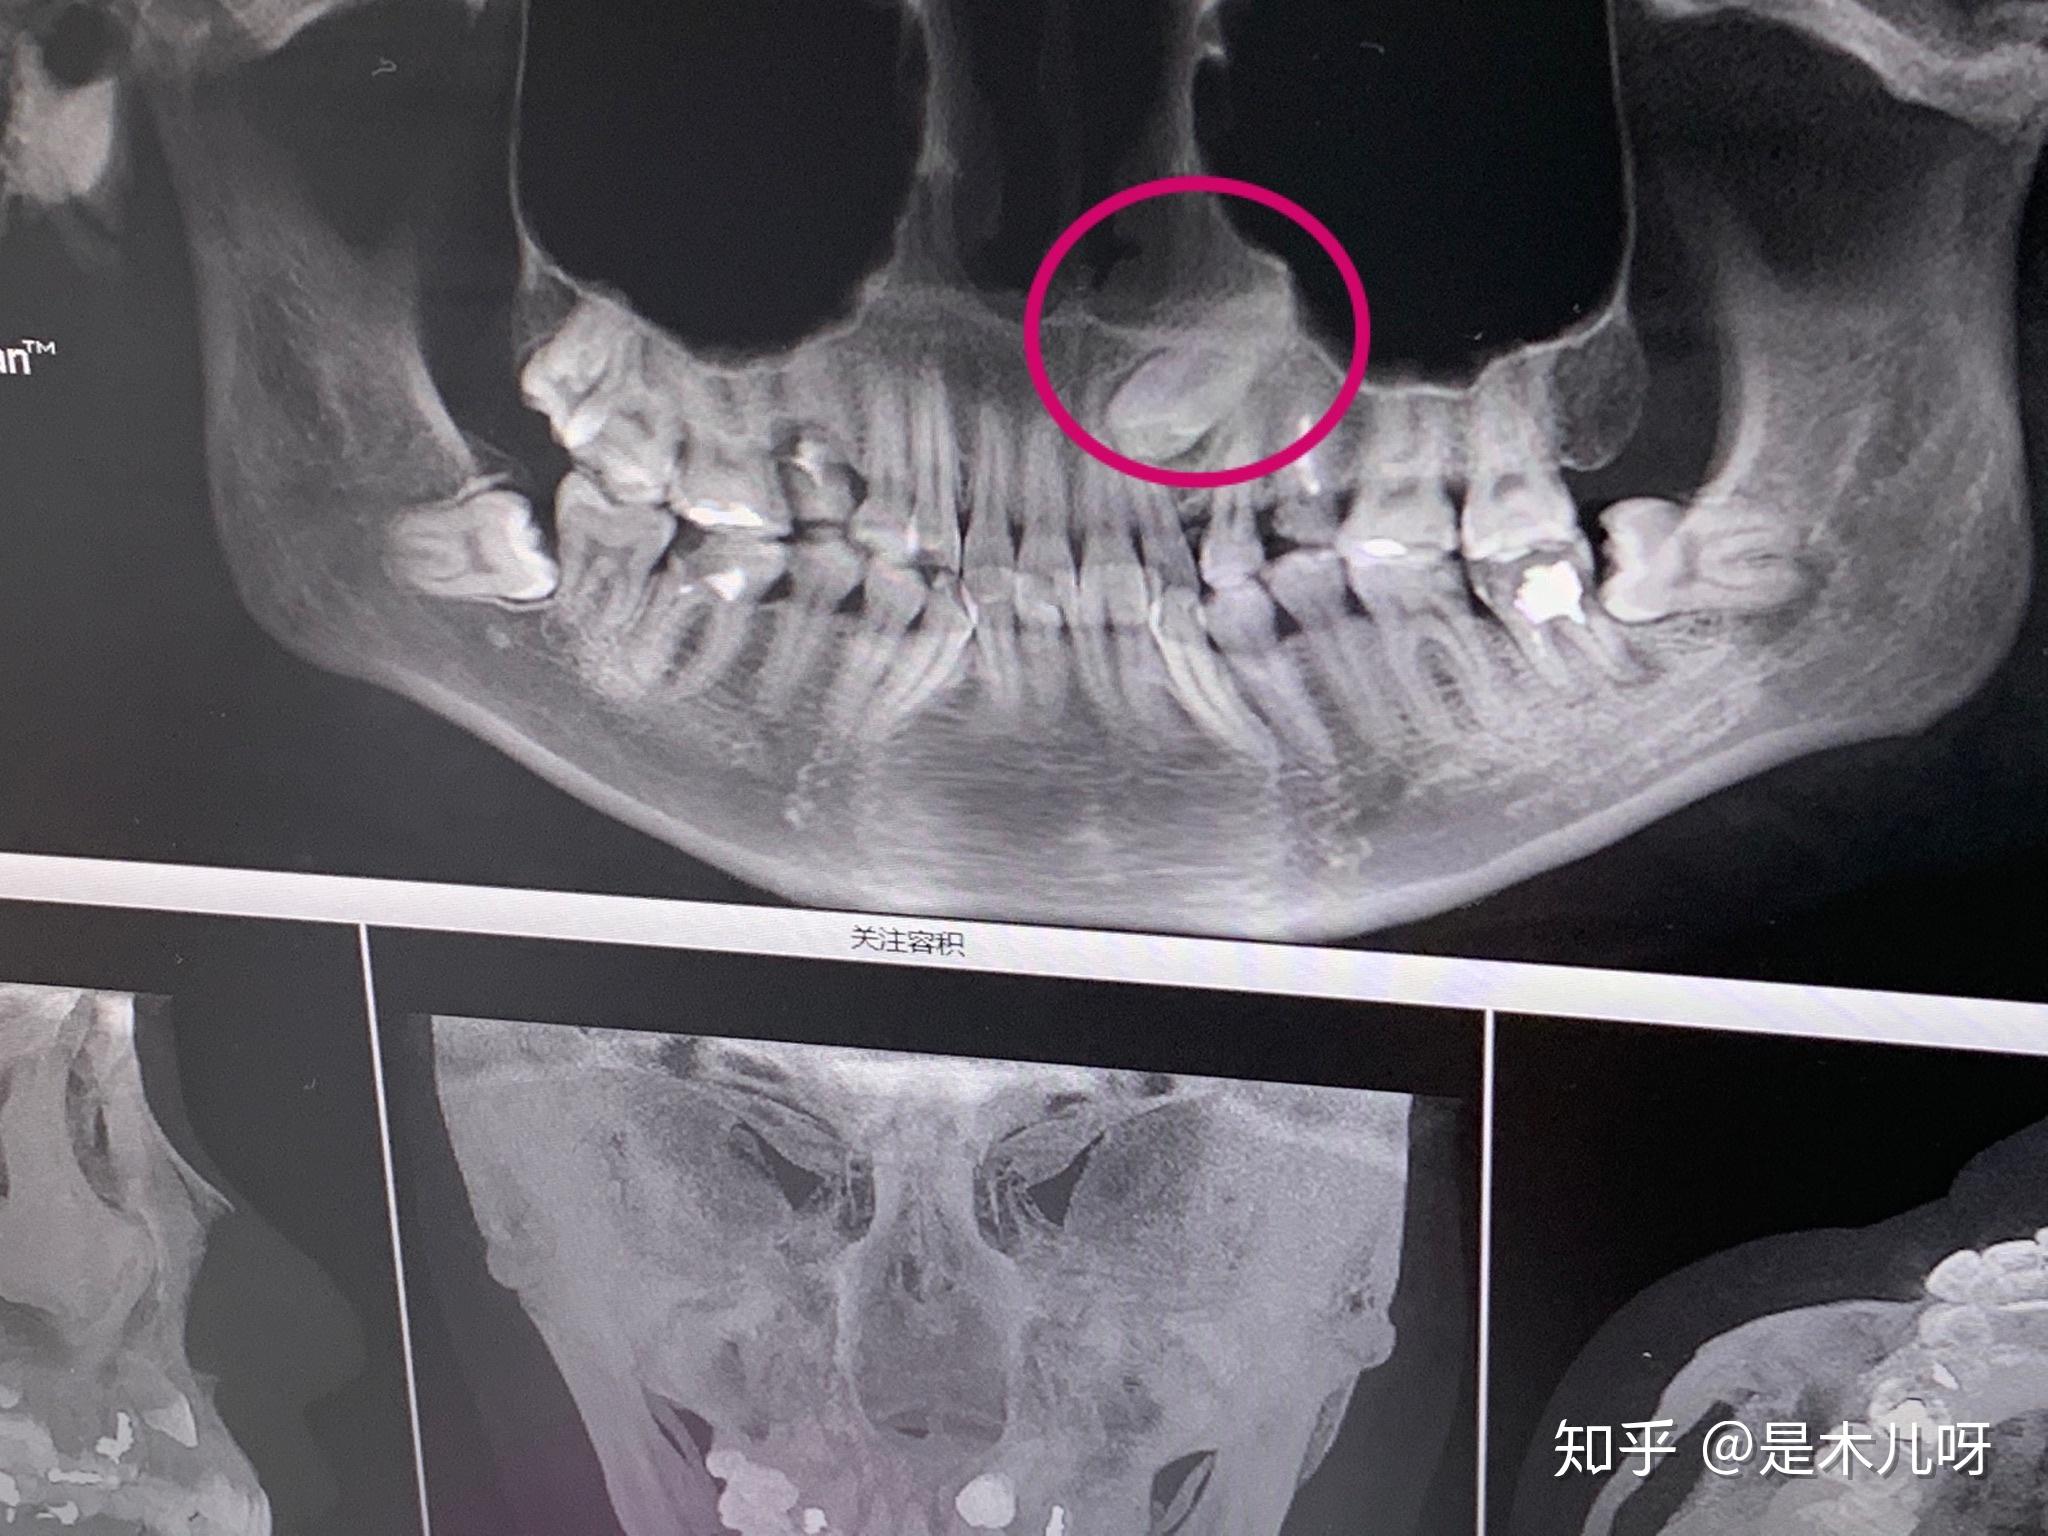

拔横着长的智齿是怎样的体验? - 知乎

图片尺寸1019x1813